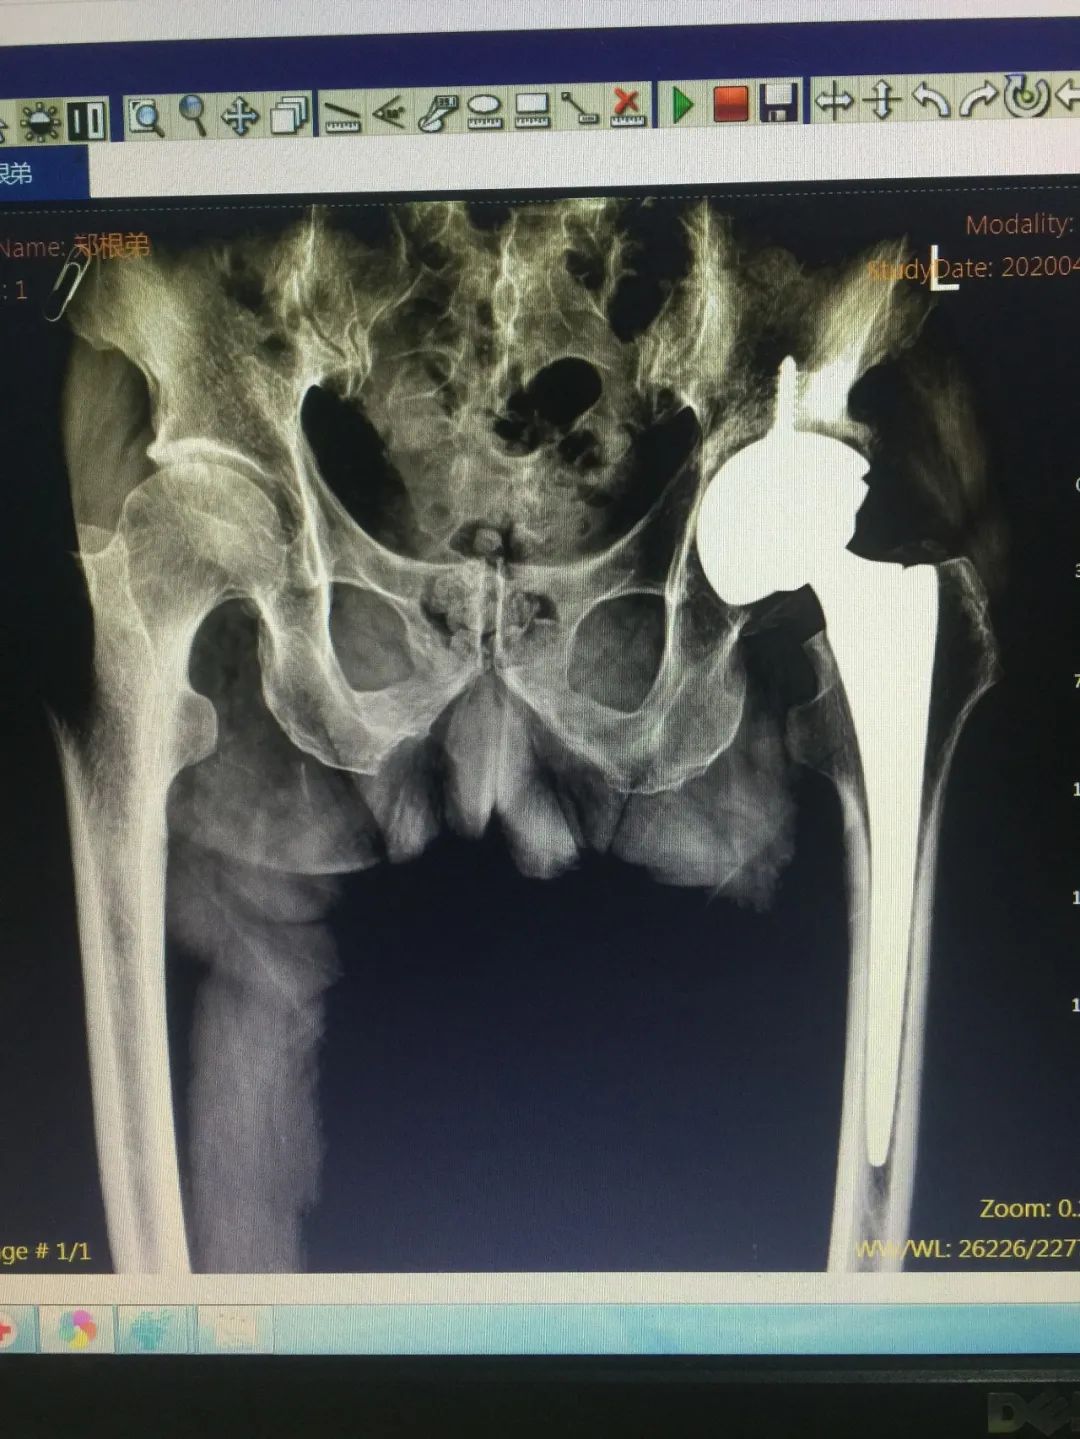

事情的原委是这样的,郑老伯今年85岁,4年前开始逐渐感觉左下肢走路时隐隐作痛,并且逐渐加重。曾经到市里几家大医院求医,医生都说老伯是因为年纪大了导致膝关节的磨损,让他吃点药,注意关节保养。但是治疗效果一直不好。随着时间的拖延,老伯的疼痛越来越严重,直到需要柱拐棍才能行走。平时身体硬朗的他心有不甘,不断地找医院求治,然而得到的答复都是膝关节老化,吃点药、打打针,但是还达不到手术的严重程度。抱着既然大医院不行,小医院也去试试看的心理,郑老伯于今年4月中旬由女儿陪着来到仁康医院,找到了徐煜院长。徐院长详细的询问了老伯的病史和整个疾病过程,仔细的给他做了检查。凭着丰富的临床经验和扎实的技术功底,徐院长敏锐地意识到郑老伯的毛病并不在膝关节,而是出在髋关节上。随后的影像检查,完全证实了徐院长的判断——左侧髋关节的严重骨关节炎,需要手术治疗。随后,郑老伯住进了病房,并由徐院长亲自操刀行全髋关节置换手术。尽管老伯的关节病变十分严重,大量的骨质增生和严重的关节变形,但是手术做得非常成功。术后在全体医护人员的精心治疗护理下,老伯术后5天就逐渐下地行走。

术前术后对比

术后四个月的行走情况